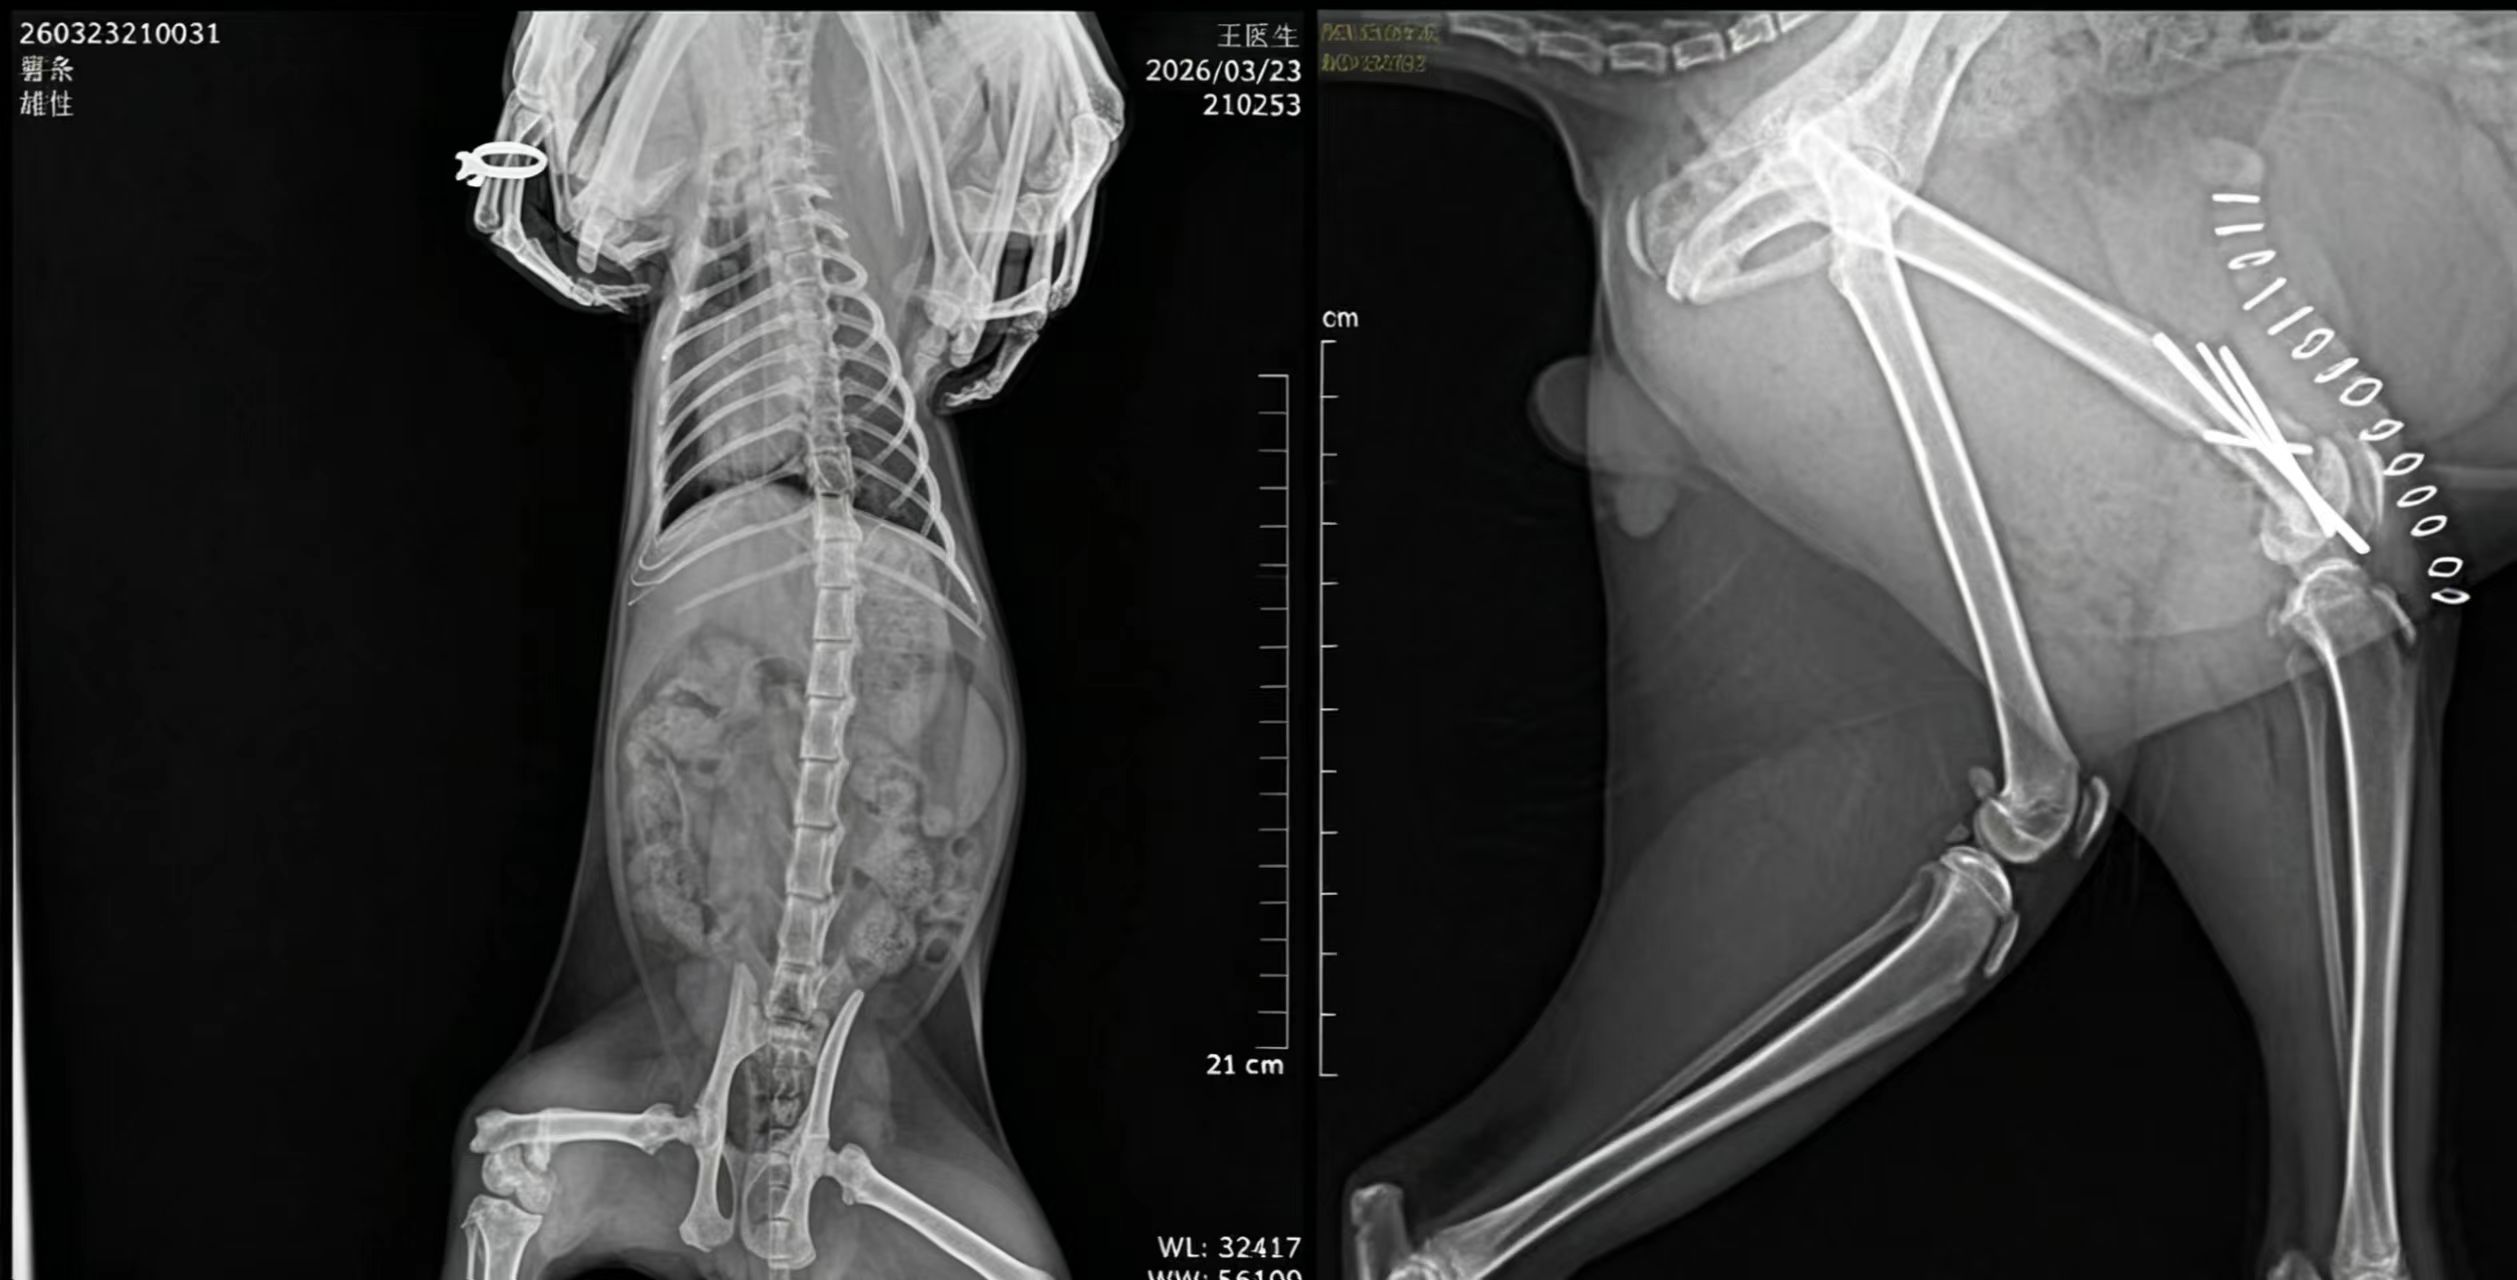

接诊后,王医生团队第一时间对猫咪进行了全面的临床检查,包括精神状态评估、心率、呼吸频率监测,同时借助DR数字成像系统进行精准影像学检查,清晰呈现出猫咪股骨远端骨折的具体位置和损伤程度——骨折端移位明显,若不及时手术干预,不仅会导致猫咪后肢畸形、终身跛行,还可能引发感染、神经损伤等一系列并发症,严重影响其后续生活质量。考虑到猫咪年仅7月龄,处于生长发育关键期,身体耐受度与成年猫咪存在差异,王医生团队结合检查结果,为其制定了个性化的手术方案,决定采用精准复位+内固定术,最大限度减少手术创伤,保障术后恢复效果。

手术前,团队严格按照诊疗规范,为猫咪进行了术前禁食禁水、血常规、肝肾功能等全面术前检查,排除麻醉风险,同时做好手术器械的无菌消毒、手术室环境净化等准备工作,确保手术全程安全可控。手术过程中,王医生凭借多年宠物外科临床经验,精准操作、细致分离软组织,小心翼翼地将移位的骨折端复位,随后采用合适规格的克氏针与接骨板进行牢固固定,避免骨折端再次移位;团队医护人员全程默契配合,密切监测猫咪的生命体征,从麻醉监护到手术操作,每一个环节都严谨细致、一丝不苟,最大限度降低手术创伤,减少猫咪的痛苦。整个手术过程顺利,耗时仅1.5小时,成功完成骨折修复与内固定。

术后3天,猫咪已能自主站立,精神状态明显好转,食欲也逐渐恢复;术后7天,伤口愈合良好,无红肿、渗液等感染迹象;术后两周复查,DR影像显示骨折端对位良好,内固定装置稳固,猫咪已能缓慢行走,逐步恢复正常活动。看着猫咪从痛苦蜷缩到重新活泼好动,宠主对王医生团队表达了深深的感谢:“多亏了宇麟宠物医院的王医生和医护团队,专业、负责、有耐心,不仅成功治好了猫咪的伤,还详细指导我们护理,让我们少走了很多弯路,选择宇麟,我们特别放心!”